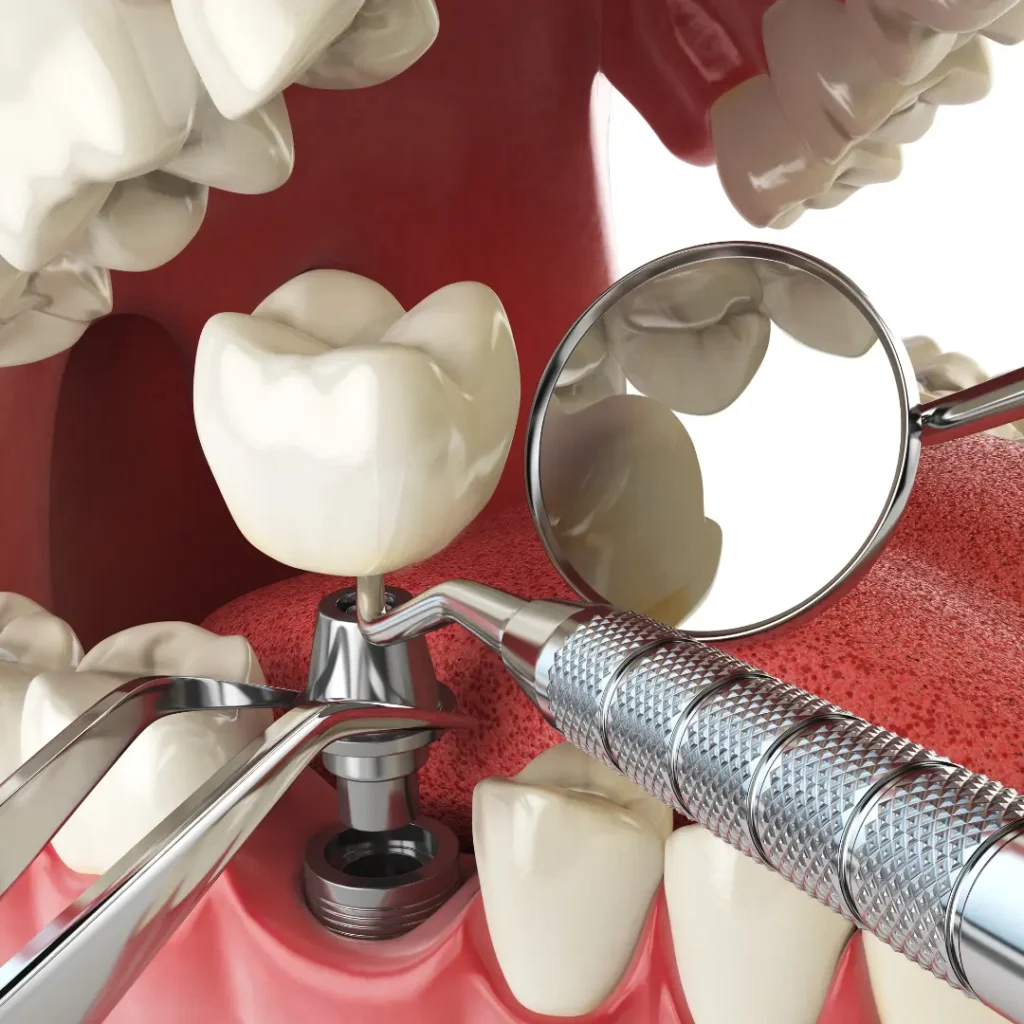

Emergency Dental Implant Services We Offer:

- Same-Day Emergency Dental Implants

- Implant Repairs & Replacements

- Loose or Broken Implant Treatment

- Emergency Extraction + Immediate Implant Options

Common Dental Implant Emergencies We Treat

Cracked or fractured implants

Loose or shifting dental implants

The implant crown fell off or broke

Infection or pain around an implant

Trauma-related tooth loss needs immediate implants

Can a damaged implant be repaired or replaced?

Yes. Depending on the issue, we may repair the implant restoration, replace the artificial tooth root, or adjust the surrounding crown or abutment. Our emergency dental services ensure quick, effective care to restore your implant.